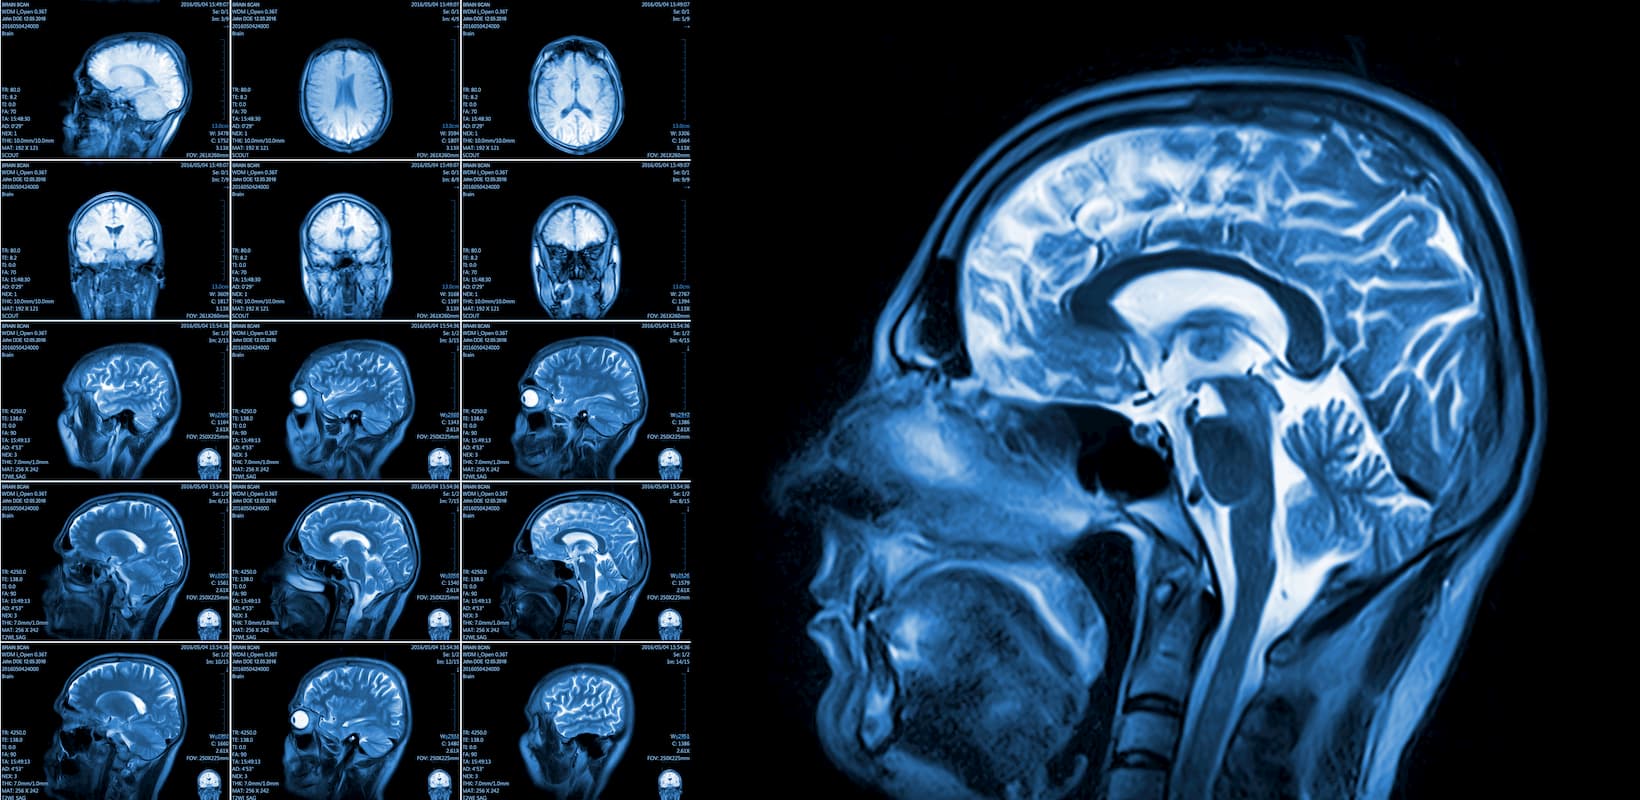

An acquired brain injury (ABI) is an injury caused to the brain since birth. There are many possible causes, including a fall, a road accident, tumour and stroke. In the UK there are approximately 350,000 NHS hospital admissions each year for all brain injuries including about 130,000 for stroke(Headway, 2016-17). Headway, the brain injury charity, provide helpful information and support in the UK for all stages of a person’s journey following a brain injury: www.headway.org.uk/about-brain-injury. Others are helpful too such as Stroke Association www.stroke.org.uk and Different Strokes www.differentstrokes.co.uk.

When the brain is damaged, it can affect both physical, cognitive and psychosocial functions of the person with the injury. Each brain injury is unique and leads to individual consequences.

A brain injury or stroke may affect several different body functions, with both visible and hidden consequences.